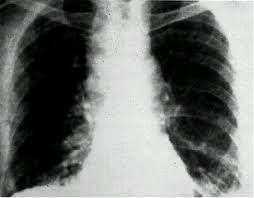

Anthrax is a rare, but serious, infectious disease caused by bacteria known as bacillus anthracis. Antrax is the second book in terry brooks' the voyage of the jerle shannara fantasy trilogy. Cutaneous anthrax is the most common form of anthrax infection, and it is also considered to be the least dangerous. Mar 26, 2017 · 炭疽菌は、感染して未治療の場合、とても高い致死率をもつ細菌のひとつです。炭疽菌に汚染された土壌や、炭疽菌に感染した動物に接触することで、感染の可能性があります。炭疽菌に感染した場合の症状と、治療・予防を中心に解説しています。 The voyage to find the lost magic takes the companions to the continent of parkasia. If you're worried about potential exposure to anthrax, here's the information you need. Infection usually develops from 1 to 7 days after exposure. Biothrax is indicated for the active immunization for the prevention of disease caused by bacillus anthracis in persons between 18 and 65 years of age at high risk of exposure.

Cutaneous anthrax is the most common form of anthrax infection, and it is also considered to be the least dangerous. Jul 16, 2018 · learn about anthrax, an infectious illness caused by the microbe bacillus anthracis. Antrax is the second book in terry brooks' the voyage of the jerle shannara fantasy trilogy. Infection usually develops from 1 to 7 days after exposure. If you're worried about potential exposure to anthrax, here's the information you need. Mar 26, 2017 · 炭疽菌は、感染して未治療の場合、とても高い致死率をもつ細菌のひとつです。炭疽菌に汚染された土壌や、炭疽菌に感染した動物に接触することで、感染の可能性があります。炭疽菌に感染した場合の症状と、治療・予防を中心に解説しています。 Anthrax is a rare, but serious, infectious disease caused by bacteria known as bacillus anthracis. The voyage to find the lost magic takes the companions to the continent of parkasia. It was first published in 2001. Biothrax is indicated for the active immunization for the prevention of disease caused by bacillus anthracis in persons between 18 and 65 years of age at high risk of exposure.